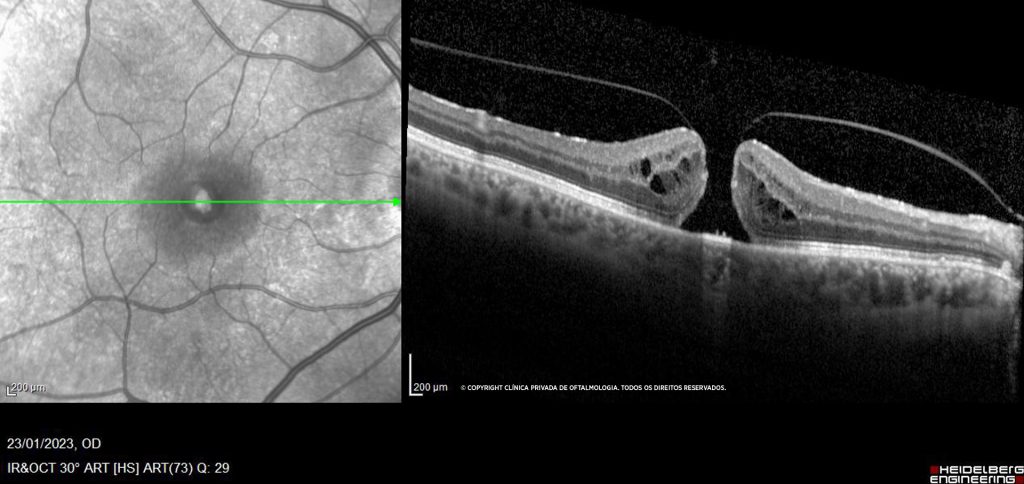

A catarata corresponde à perda de transparência da lente natural do olho (o cristalino). A sua formação é geralmente progressiva instalando-se inicialmente uma perda de qualidade de visão.

O que é a catarata? O termo catarata refere-se à opacificação da lente natural do nosso olho (o cristalino), que vai perdendo transparência. Este processo é o resultado de mudanças biológicas e bioquímicas que ocorrem nas fibras do cristalino. Quais são as causas…